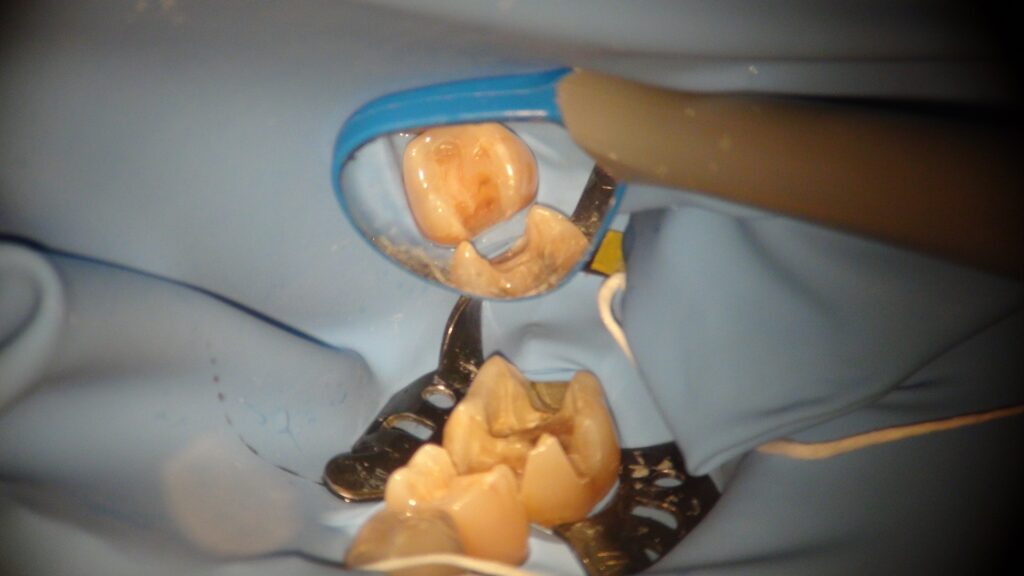

むし歯を取り除いていくと こんな感じになっていました。

取り終わったところで、ラバーダム。

ラバーダムができる場合は、やるとこちらも治療操作が楽になることがあります。

ラバーかけているところと、レジンを詰めたところ。